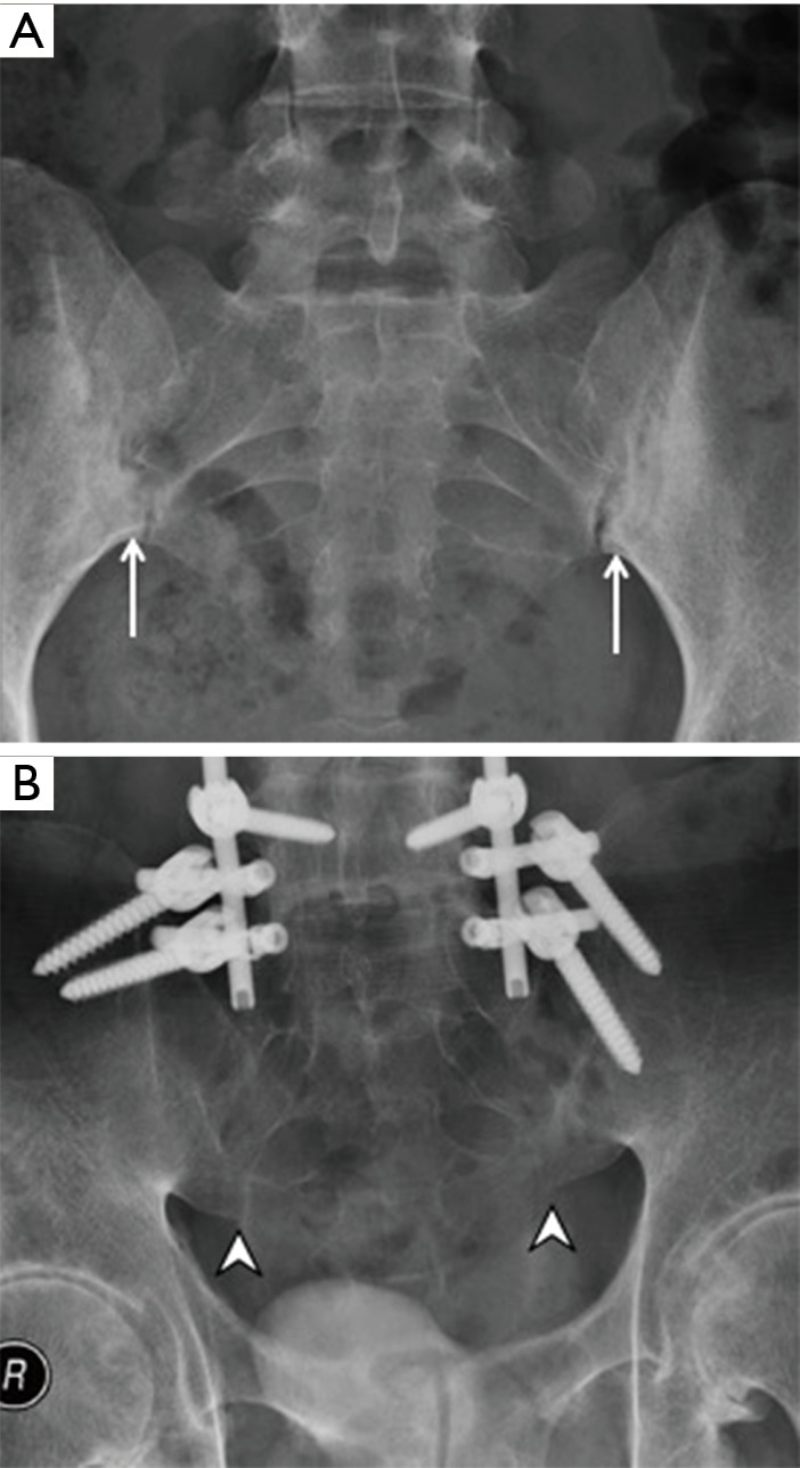

Hình ảnh viêm khớp cùng chậu gậy cứng khớp

Hình ảnh viêm khớp cùng chậu cho thấy viêm khớp cùng chậu khiến khớp cùng chậu dính hoàn toàn

Viêm khớp cùng chậu gây xơ cứng

Viêm khớp cùng chậu (hình A) gây xơ cứng và xói mòn dưới sụn (dấu mũi tên) và dính khớp (hình B)